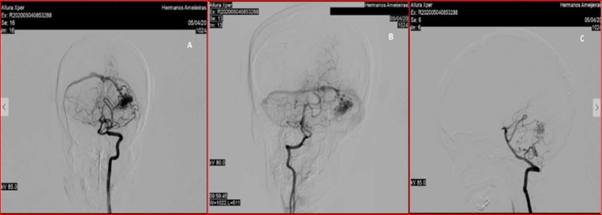

A 26-year-old female patient, Karnofsky index4 90 points. She abruptly presented intense headache, vomiting, and photophobia. In the initial brain computed tomography (CT scan), haemorrhage is objective in the left cerebellar hemisphere, entering the Intensive Care Unit. At 24 hours, it presents degradation of the state of consciousness due to obstructive triventricular hydrocephaly. It is decided to place peritoneal ventricular derivative system with medium-pressure opening valve and evidence of neurological event resolution. Within 15 days of the onset of symptoms in the study of Angio CT scan, arteriovenous malformation (AVM) is diagnosed in the left cerebellar hemisphere, DSA (Figure 1 A, B and C) and two-dimensional tissue perfusion are performed (Figures 2 & 3).

Figure 1 Arteriography by digital subtraction. Injection from left and right vertebral territories. A-Vista frontal, B-oblicua and C- lateral, respectively. The VMA vascular buckle is visualised, in this case with high flow with multiple aferences from the posteroinferior cerebellar artery (PICA), anteroinferior cerebellar artery (AICA) and upper cerebellar artery, with early venous drainage to left transverse sinus already evident from the arterial phase itself.